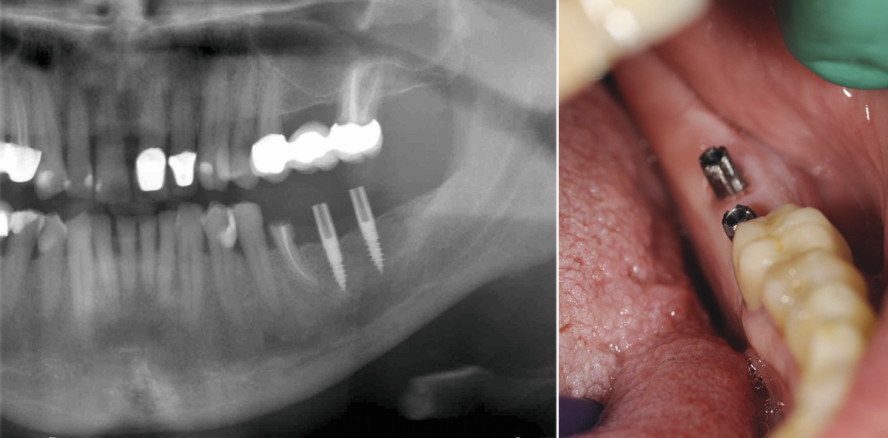

Nachfolgend wurde eine Röntgenkontrolle mittels OPG durchgeführt. Dabei lag der Fokus vor allem auf der Lage

der Implantate zum Nervus mandibularis sowie Foramen mentalis. Auch die Implantattiefe im Knochen wurde dokumentiert (Abb. 8). Eventuelle Korrekturen (Nachdrehen) sind im Anschluss möglich. Gegebenenfalls werden diese Änderungen dann im OP-Protokoll

festgehalten. Nach der OPG-Kontrolle erfolgte das Aufbringen und Anpassen der PEEK-Abformkappen sowie